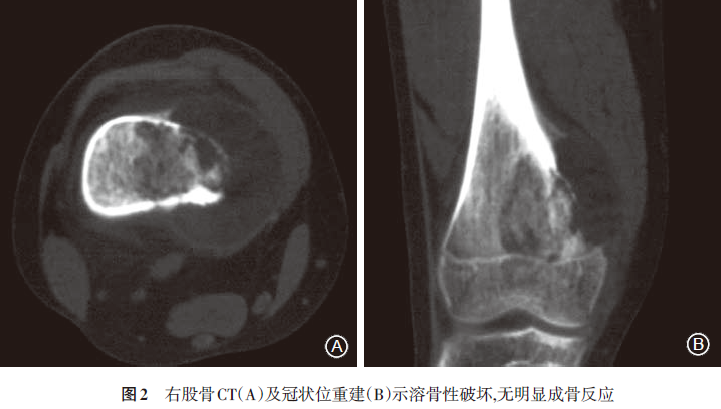

显示心、肺、膈均未见明显异常。正、侧位X线片(2008.6.14)示右股骨远端可见半圆形骨破坏区,骨小梁及内侧骨皮质破坏,边界模糊,内侧缘三角形骨膜反应,局部软组织肿块,提示右股骨恶性肿瘤,膝关节未见明显异常(图1)。CT(2008.6.17)示右侧股骨下段干骺端骨质密度不均匀,内侧骨皮质破坏,骨膜增厚外突(图2)。MRI(2008.6.16)示右侧股骨远端干骺端内侧见骨质破坏,周围见软组织肿块影;T1加权像呈等低信号,T2加权像呈稍高信号,病灶周围见骨膜反应并可见Codman三角,注射造影剂后见轻度对比增强(图3)。ECT(2008.6.17)静脉注射骨显像剂3h后行全身前后位骨显像,骨显像尚清晰,右侧股骨下段可见局部放射性异常浓聚,余未见明显异常放射性浓聚或稀疏缺损区(图4)。